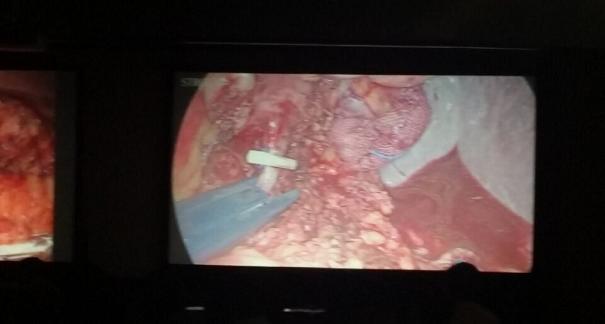

2015年10月23-25日,河北省醫(yī)學(xué)會(huì)肝膽外科學(xué)術(shù)年會(huì)在河北省石家莊市頤園賓館隆重召開。本次學(xué)術(shù)會(huì)議河北省醫(yī)學(xué)會(huì)特邀了北京301總院的胡明根教授、天津第一中心醫(yī)院的張雅敏教授、山西醫(yī)大醫(yī)院的趙浩亮、河北醫(yī)科大學(xué)第二醫(yī)院劉建華教授等國內(nèi)知名專家參會(huì)。參加會(huì)議的醫(yī)院達(dá)100余家,近300名肝膽外科的臨床專家和一線醫(yī)生們親臨會(huì)場(chǎng),在此進(jìn)行廣泛的學(xué)術(shù)交流。25號(hào)全天會(huì)議安排了五臺(tái)手術(shù)視頻演示,全體參會(huì)人員進(jìn)行觀摩,并實(shí)時(shí)提問,進(jìn)行手術(shù)交流。演示手術(shù)包括腹腔鏡胰、十二指腸切除術(shù)、腹腔鏡左、右半肝切除術(shù)、腹腔鏡門脈高壓癥的治療、兩鏡或三鏡聯(lián)合膽石癥的治療、開腹胰、十二指腸切除術(shù)、手術(shù)演示中多次使用了我公司產(chǎn)品速豐(可吸收止血結(jié)扎夾),產(chǎn)品使用滿意度受到專家們的一致好評(píng)。